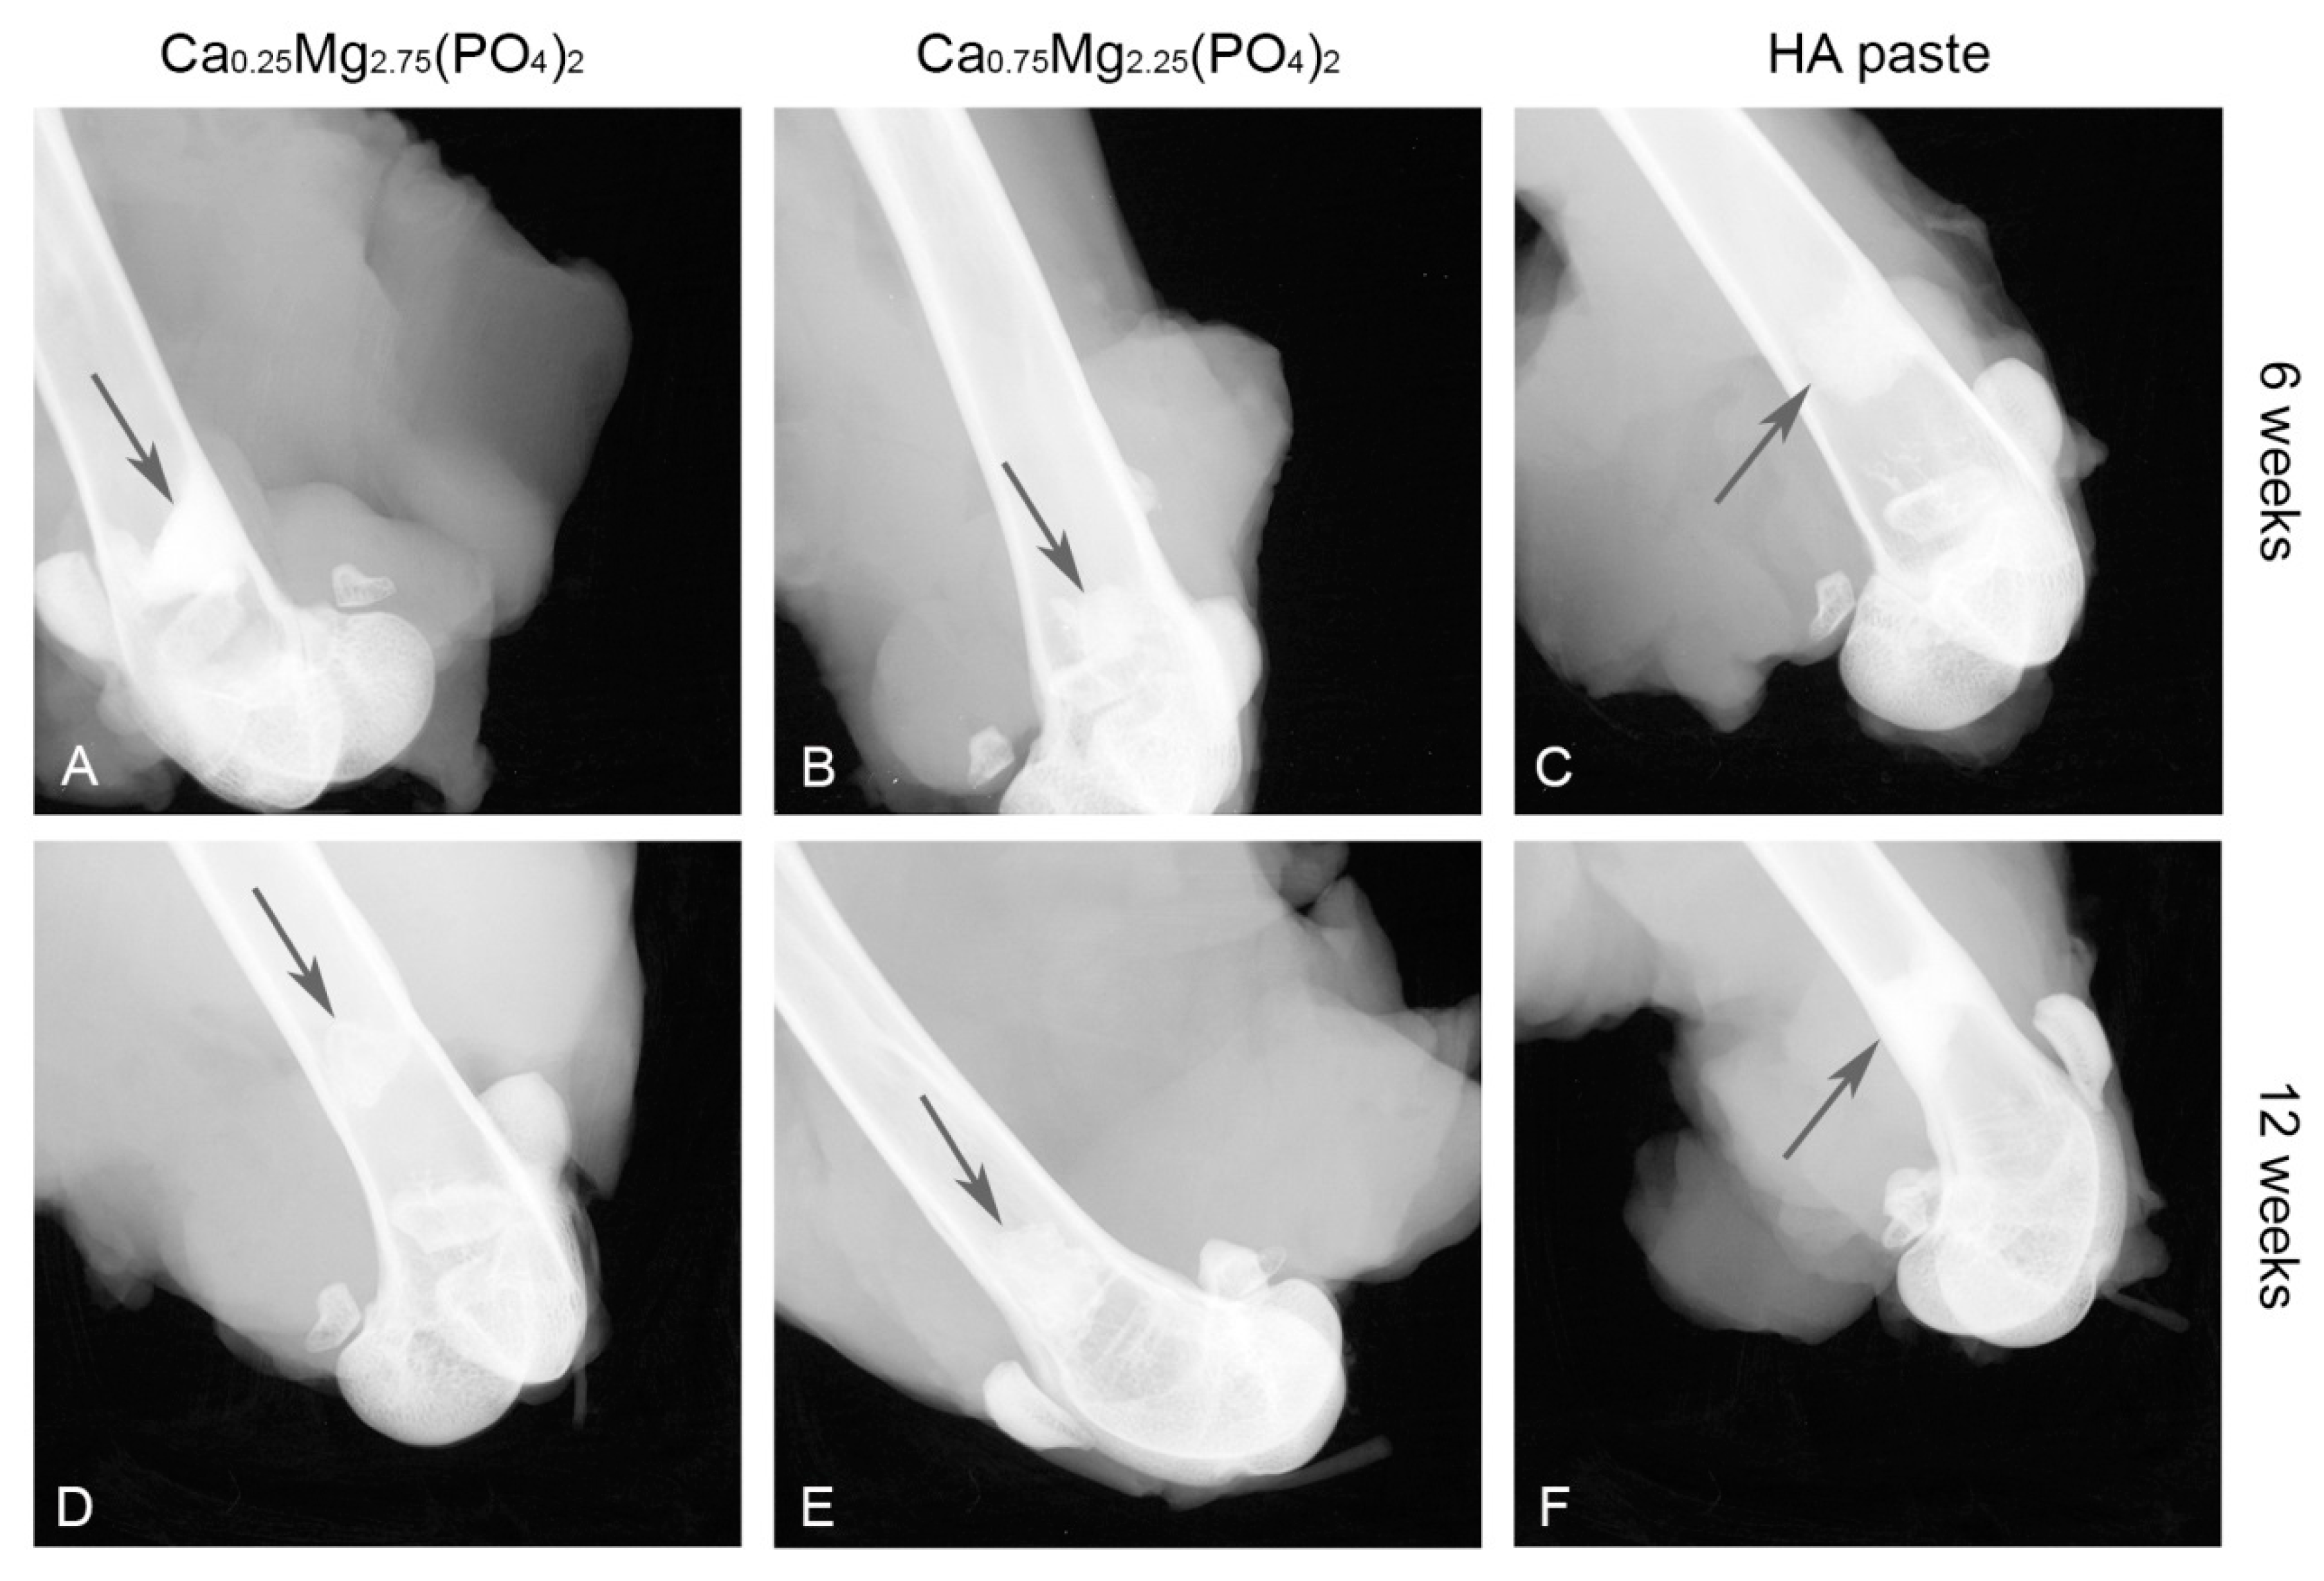

X-ray imaging revealed, that the HA paste showed no difference in X-ray opacity when comparing 6 weeks and 12 weeks post-implantation (Figure 5C,F). In contrast, X-ray opacity decreased for the Ca0,25Mg2,75(PO4)2 paste (Figure 5A,D) and also for the Ca0,75Mg2,25(PO4)2 paste (Figure 5B,E).

In vivo, both CaMgP cement pastes induced vital bone formation according to the results of the histological analysis of the implants. A fast initial ingrowth of vivid bone cells into the medullary cavity resulted in a complete regeneration of the femur corticalis within the drill hole region after 12 weeks. Similar results have already been presented for MPCs in an ovine femoral defect model, where struvite cements displayed almost complete degradation after 10 months accompanied by new bone formation [7]. MPCs have also been subject to studies in rodents, where 3D printed scaffolds were implanted in a rat calvaria defect model leading to enhanced bone regeneration, even with partially increased bone volume [31]. During the bone regeneration process, the CaMgP cement pastes in the current study were completely surrounded by newly formed bone tissue, whereas the initial bone-implant contact (6 weeks) was higher compared to the HA paste. Furthermore, the implants gradually decreased in size until the end of the experiment (12 weeks), most likely due to resorption processes, which may also explain the more fissured surface of the samples compared to the reference paste. In addition, decrease of X-ray opacity supported the finding that the CaMgP cements were successively degraded in vivo. Radiographic changes indicating a faster and more distinct dissolution of MPCs compared to CaP based cements in heterotopic rodent models have already been reported previously [32]. While the bone-implant contact was increasing for Ca0.75Mg2.25(PO4)2 from 6 to 12 weeks, the opposite was observed for the Ca0.25Mg2.75(PO4)2 paste, which might be related to the fast degradation of the material. In this case, bone ingrowth might not have been able to keep up with the speed of material degradation and close bone- or osteoid-implant contact couldn’t be achieved. On the other hand, a slightly higher osteoid-percentage observed for Ca0.25Mg2.75(PO4)2 may indicate a better stimulation of bone growth compared to the Ca0.75Mg2.25(PO4)2 paste. The HA paste showed similar osseointegration as the CaMgP materials with good bone-implant contact. However, as expected, only marginal degradation of the paste was observed after 6 and 12 weeks, which is in accordance with results reported in the literature [33]. Additionally, this was supported by X-ray imaging, which revealed practically no change in X-ray opacity during this time period, indicating the absence of any resorption effects.

Figure 5. X-ray images of the Ca0,25Mg2,75(PO4)2 paste (A,D), the Ca0,75Mg2,25(PO4)2 paste (B,E) and HA paste (C,F) in the femoral defect directly after explantation after 6 and 12 weeks. The implants are marked by arrows.